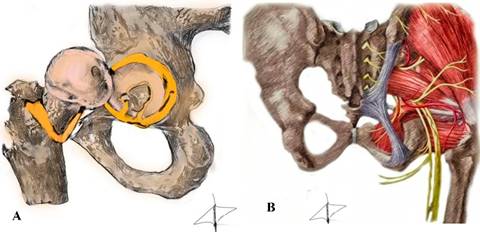

Bryan Kelly, realizó una descripción topográfica y anatómica del abordaje de la cadera dolorosa de acuerdo con la teoría o sistema de las capas, las cuales se describen de manera breve a continuación (Tabla 1 y Figura 1).1

Tabla 1: Sistema de capas de Bryan Kelly.13

| Capa | Estructura | Región anatómica | Biomecánica y función | Patología |

|---|---|---|---|---|

| I | Osteocondral | Cabeza femoral, acetábulo | Congruencia articular y movilidad cinemática | Displasia, anteversiones y antetorsiones |

| II | Inerte | Cápsula, labrum, complejos ligamentarios | Estabilidad estática | Coxa profunda, desgarros labrales, inestabilidad capsular, capsulitis adhesiva |

| III | Contráctil | Músculos que pasan a través de la cadera, músculos lumbosacros, piso pélvico | Estabilidad dinámica | Pubalgia, entesopatías, psoitis, pinzamiento de recto femoral, tendinopatías (add, gluteus) |

| IV | Neuromecánico | Mecanismo toracolumbar, estructuras neurovasculares | Secuencia de la cadena cinemática abierta y cerrada | Síndrome glúteo profundo, disfunción neuromuscular |

Capa I o capa osteocondral. Estructuralmente formada por el par fémur y acetábulo, cuya función es la congruencia articular. La modificación o cambio estructural en alguno de los dos componentes, llevará a patologías que originen cadera dolorosa, ya sea por patologías del desarrollo como displasia femoral o acetabular; cambios en la anteversión o antetorsión; inclinación acetabular y profundidad del mismo; o bien, cambios estructurales dinámicos como el pinzamiento tipo cam, pincer o mixto; pinzamiento trocantérico, subespinoso o delaminación. Sin embargo, los cambios en el desarrollo evolucionan a cambios dinámicos.

De igual manera, los cambios en la capa I repercuten a cambios y patologías en las demás capas; por ejemplo, en la II provocan lesiones labrales o inestabilidad capsular y, a su vez, cambios en capa III como resultado de cambios en el eje de rotación de la cadera lo que ocasiona provoca alteraciones de la estabilidad dinámica. Esto quiere decir que, gran parte de las ocasiones, el abordaje de la cadera dolorosa llegar a ser de capas mixtas a pesar de que el origen de la misma sea en una capa en específica.1

Capa II o inerte. Referente a ésta, se encuentran el labrum acetabular, la capsula articular, el complejo ligamentario (iliofemoral o Y de Bigelow, pubofemoral, isquiofemoral y el ligamento redondo o teres). Su función biomecánica es la estabilidad estática de la cadera.

Al igual que en la capa I, las patologías etiológicas de capa II no se comportan de manera independiente y única, sino como el todo en un sistema, ya que la pérdida de estabilidad estática −ya sea por desgarros labrales, capsulares, lesiones ligamentarias o pérdida de la presión negativa que provoca un medio de contención de la cadera− puede llegar a ocasionar un desplazamiento del centro de rotación de hasta 2-5 mm, lo que genera estrés y falla en la biomecánica contráctil, originando alteración en la capa III, que se puede traducir en osteoartritis de cadera por una incongruencia femoroacetabular (capa I).2

Se ha descrito que el ligamento iliofemoral es el más fuerte de los tres. Éste provee estabilidad a la rotación externa y previenen la traslación de la cabeza femoral hacia anterior; el ligamento redondo previene la traslación inferior; el ligamento pubofemoral, la traslación posterior y estabilidad en flexión; y el ligamento isquiofemoral provee estabilidad a la rotación interna.1

Capa III o contráctil. En ésta podemos encontrar a los estabilizadores dinámicos de la cadera, cuya contracción y relajación sinérgica proveen de movilidad y control activo a la misma. En ella se encuentra la musculatura pelvitrocantérea, los estabilizadores del suelo pélvico, aductores y flexores de cadera. Patologías tan frecuentes y subdiagnosticadas en esta estructura de la cadera son una de las causas principales de «la cadera dolorosa», como es el caso de la coxa saltans o snapping, que ocurre con el psoas y la eminencia iliopectínea en distintos grados de flexión y rotación de la cadera.

Lesiones en la musculatura pelvitrocantérea, ya sea traumática, iatrogénica o degenerativa, por ejemplo, de glúteo medio y menor, se traducen con debilidad del mismo y provoca marcha en Trendelenburg y signo de Trendelenburg, lo que ocasiona cambios en el eje de rotación de la cadera y, a largo plazo, cambios estructurales y dinámicos que provocan artrosis y dolor de cadera. Dentro de esta capa, también podemos encontrar alteraciones en el suelo pélvico como hernias, que a pesar de no ser per se patología de cadera, el dolor referido o localizado es hacia la misma.2

Capa IV o neuromecánica. Es la capa estructuralmente compleja, encargada de la cadena cinemática cerrada y abierta de la cadera, con componentes neurovasculares, mecanorreceptores y nociceptivos encargados de mantener la función dinámica y estática de la cadera y la de los componentes de las demás capas.

A grandes rasgos, esta capa se refiere a la posición y postura de la pelvis sobre el fémur. Dicho esto, la capa IV puede ser comprometida por patologías de origen lumbar, sacro o bien puramente neurológico; así como cambios estructurales y de alineación a distancia como varo valgo, antecurvatum o recurvatum de rodilla o bien cambios estructurales y de alineación del pie y tobillo.6

Los neurorreceptores de esta capa son los de Ruffini o tipo I, localizados en la cápsula, periostio, ligamentos y tendones cuya función es la propioceptiva; los tipo II o corpúsculos de Pacini y Meissner, se localizan en la cápsula profunda y en los cojinetes grasos periarticulares, encargados de la cinestesia; los tipo III también llamados terminaciones de Golgi, se encuentran en los ligamentos tanto extrínsecos como intrínsecos cuya función es la propiocepción; y finalmente, los tipo IV o terminaciones nerviosas libres se encuentran en la periferia de la cápsula articular, vasos sanguíneos y cojinetes grasos responsables del dolor y nocicepción.